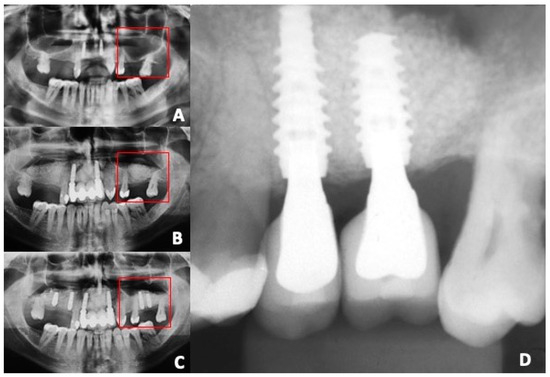

- This retrospective study, at the one-year follow-up, found that 70% hydroxyapatite (HA) and 30% beta-tricalcium phosphate (β-TCP) provided stable bone support for titanium dental implants made using additive manufacturing. Plenum Oss, a synthetic biphasic bone graft material, allowed significant bone regeneration in the maxillary sinus, making it easier to place dental implants that achieved excellent osseointegration. The additive-manufactured grade-23 titanium implants had a survival rate of 97.43% after one year of loading in grafted areas.

- The additive manufacturing process for the titanium implants produced a complex topography and rough surface, which provided ideal bone anchorage, even in low-density bone. This contributed to the excellent clinical results, with an average distance to the first bone contact of only 0.23 mm, and no instances of implant failure or peri-implant infections among the remaining 38 successful fixtures.